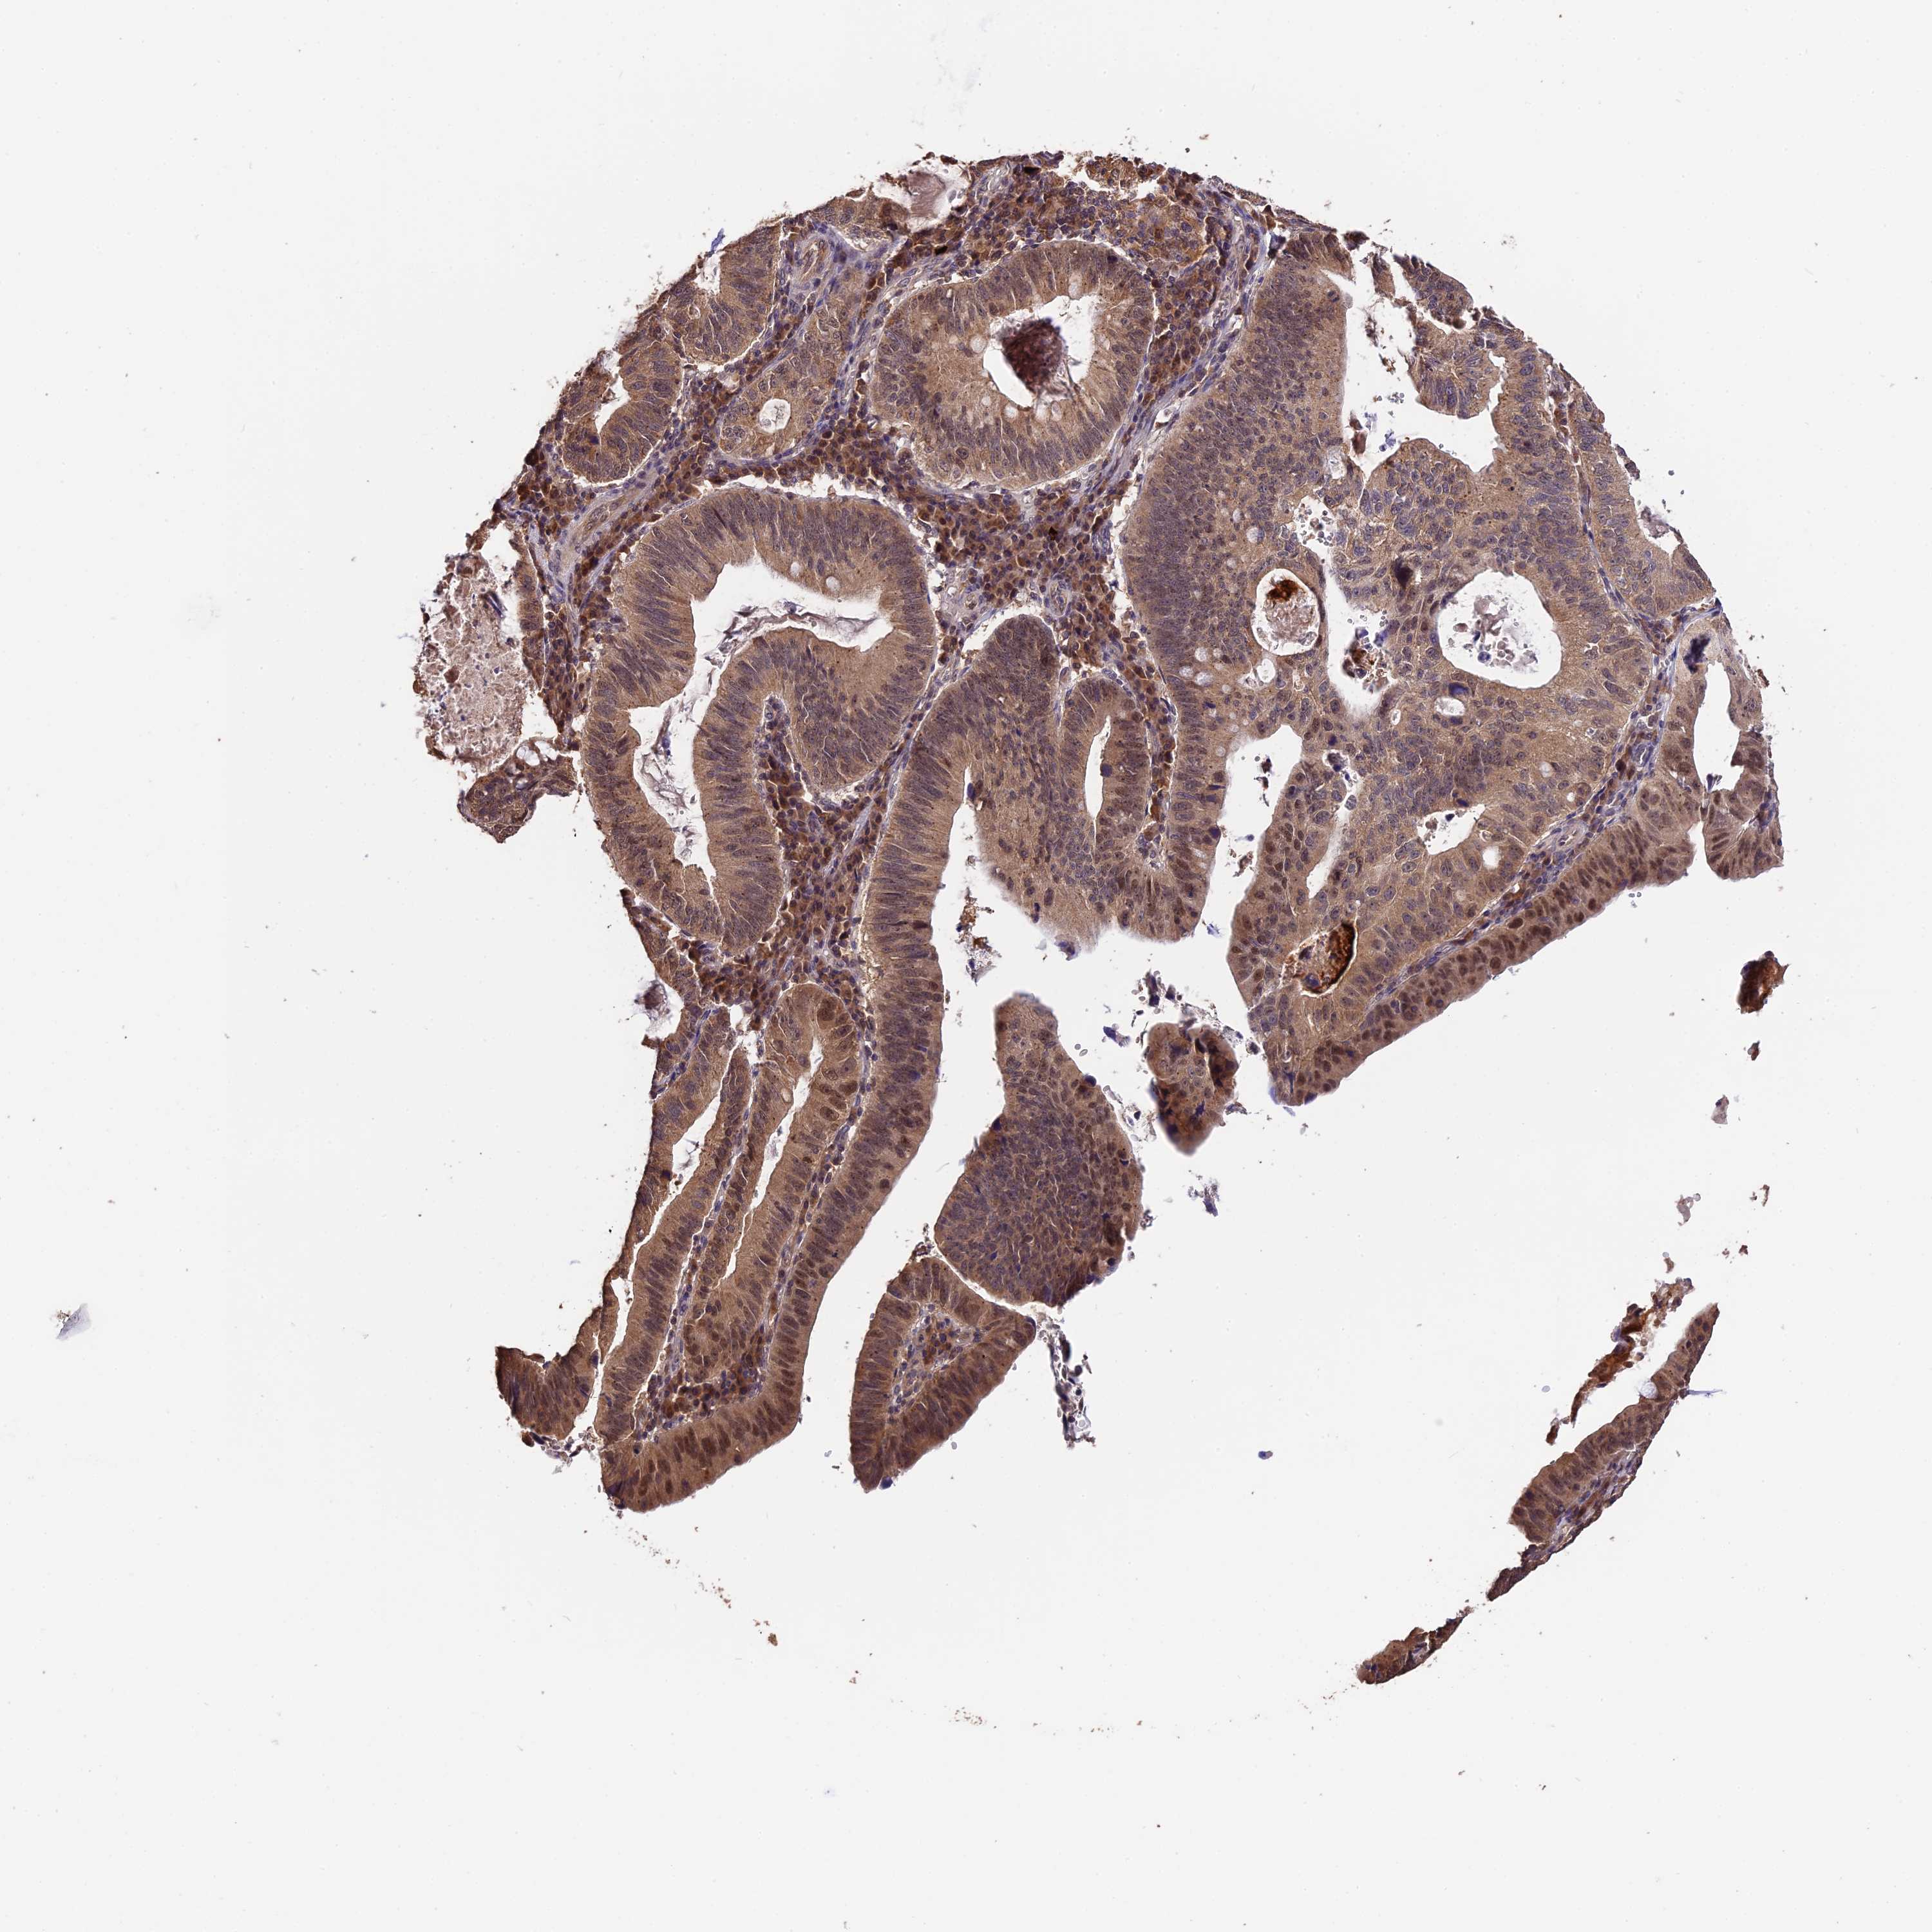

STOMACH CANCER - Protein expressioni

A mouse-over function shows sample information and annotation data. Click on an image to view it in a full screen mode. Samples can be filtered based on level of antibody staining by selecting one or several of the following categories: high, medium, low and not detected. The assay and annotation is described here.

Note that samples used for immunohistochemistry by the Human Protein Atlas do not correspond to samples in the TCGA dataset.

Antibody stainingi

Antibody staining in the annotated cell types in the current human tissue is reported as not detected, low, medium, or high, based on conventional immunohistochemistry profiling in selected tissues. This score is based on the combination of the staining intensity and fraction of stained cells.

Each image is clickable and will lead to virtual microscopy that enables deeper exploration of all samples and also displays staining intensity scores, fraction scores and subcellular localization as well as patient and tissue information for each sample.

Antibody HPA041130

Antibody HPA041380

Staining

High

Medium

Low

Not detected

Intensity

Strong

Moderate

Weak

Negative

Quantity

>75%

75%-25%

<25%

None

Location

Nuclear

Cytoplasmic/membranous

Cytoplasmic/membranous,nuclear

Adenocarcinoma, NOS